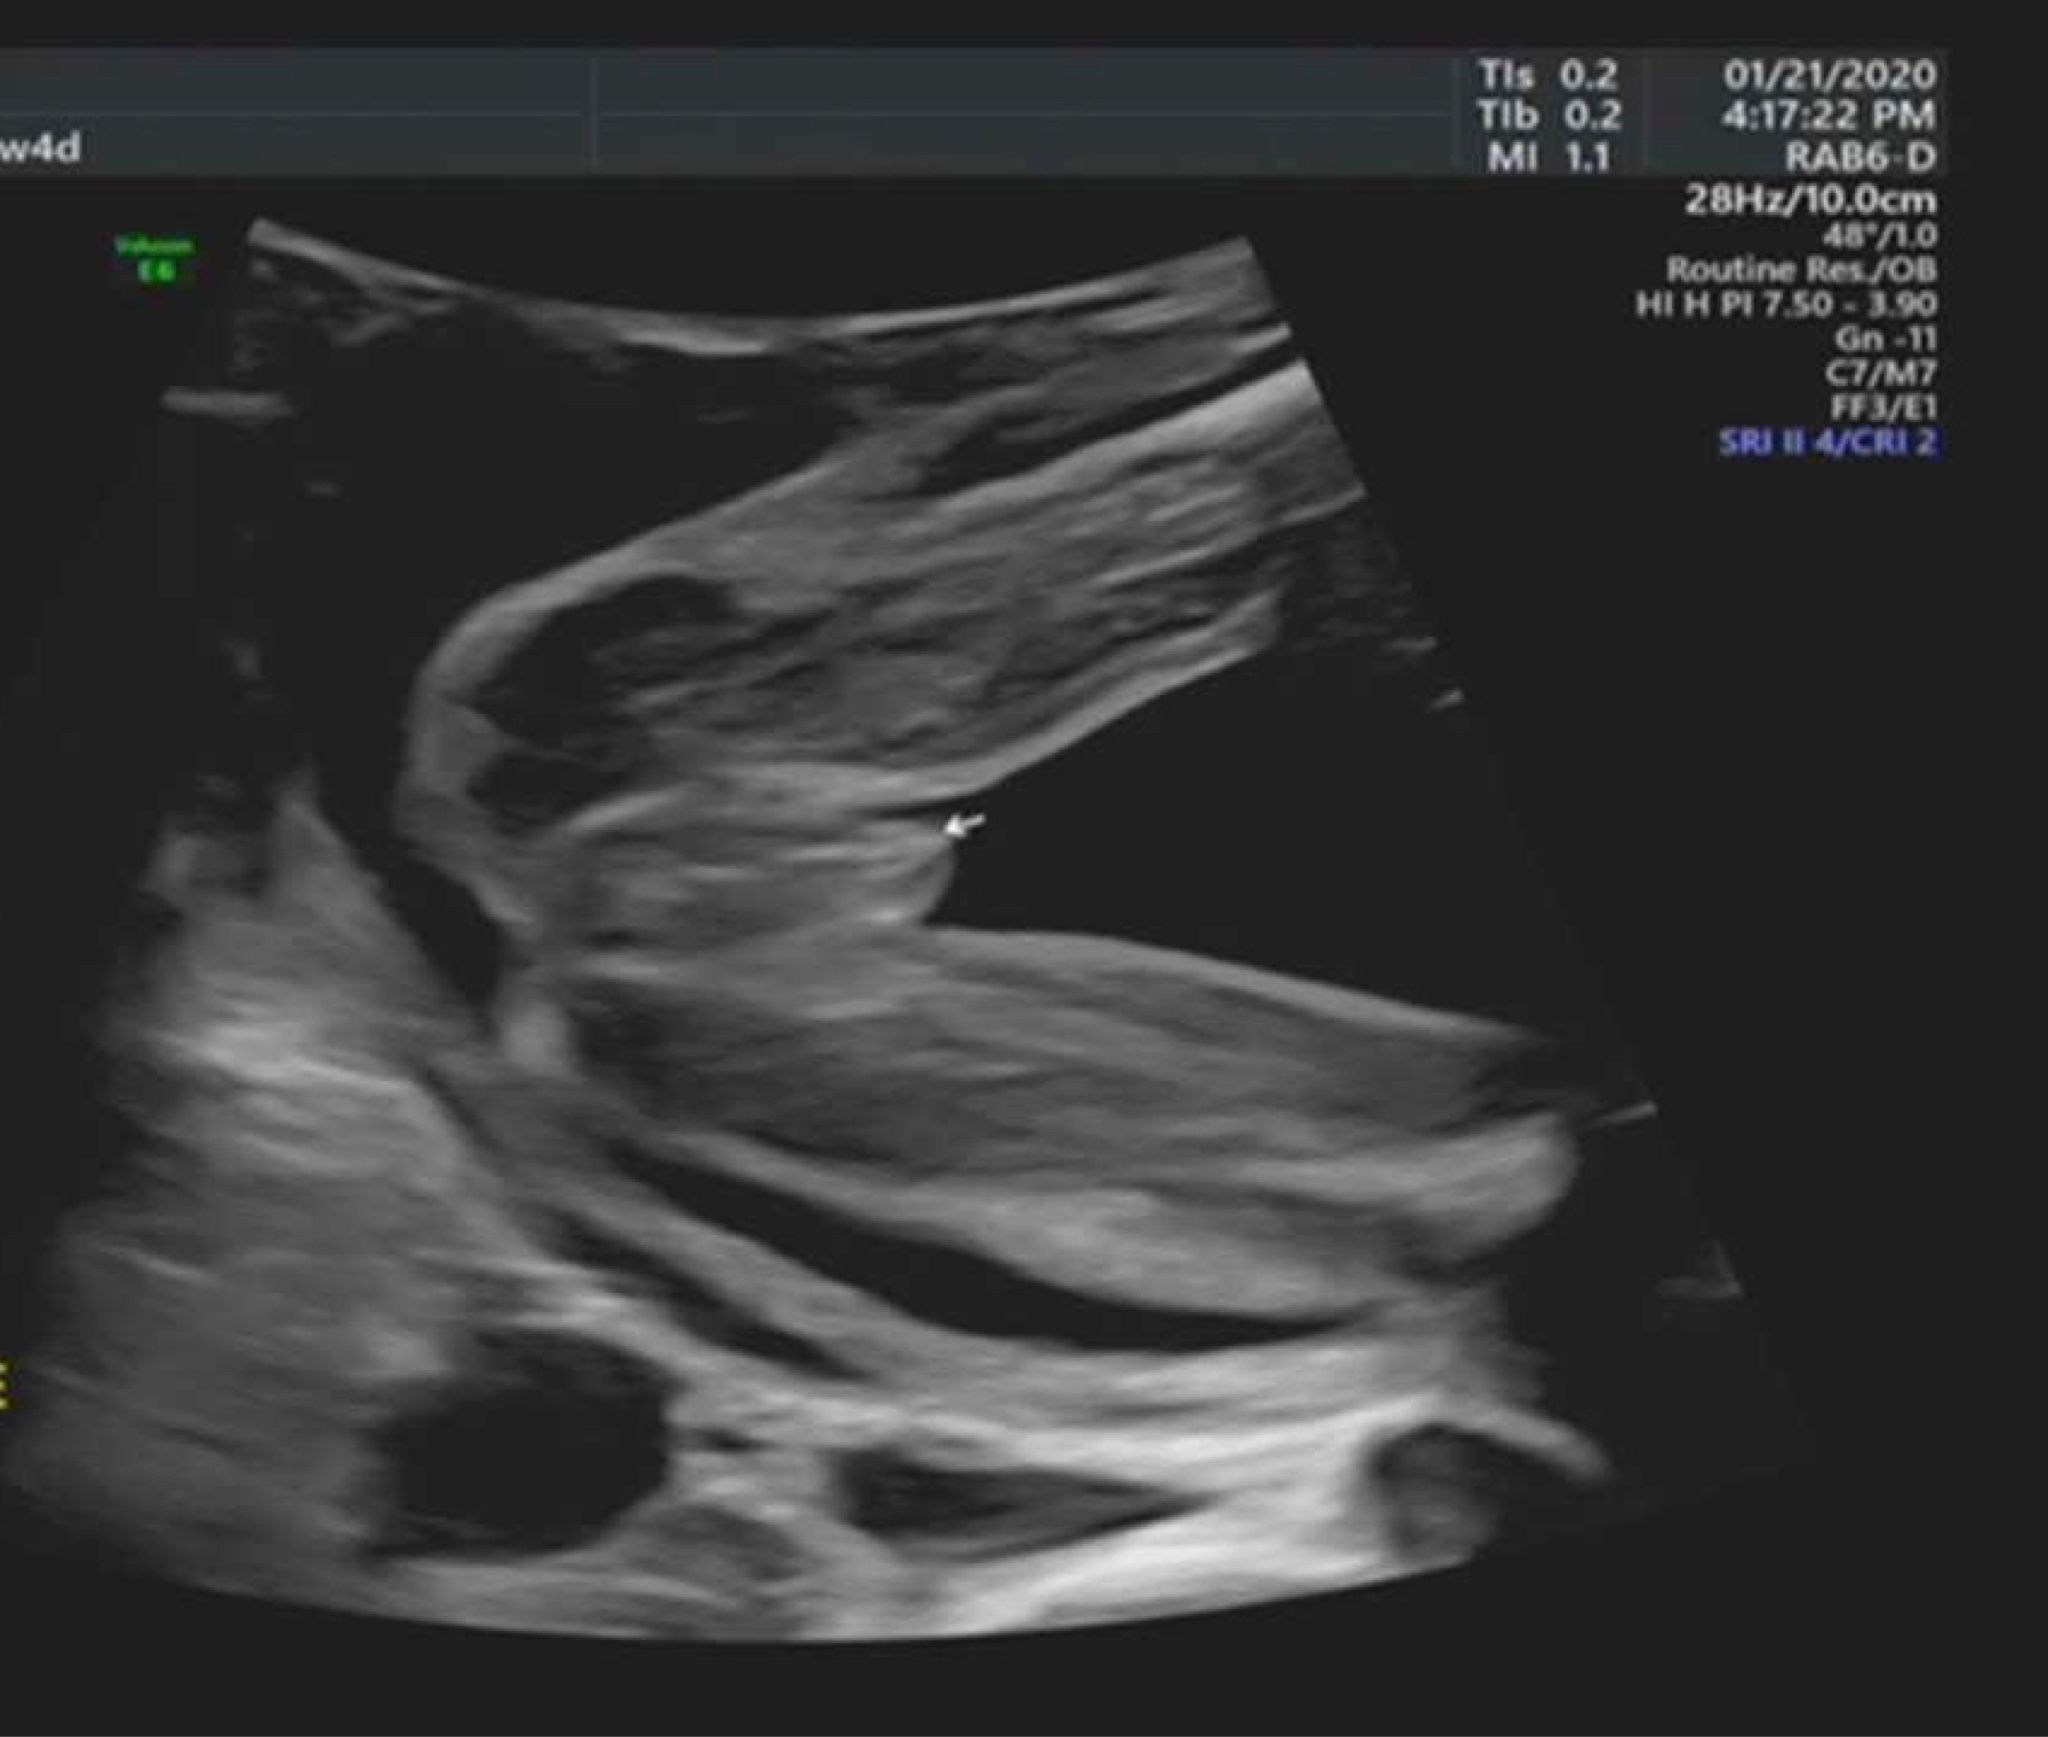

可以請各位媽媽幫我看這是男生還是女生嗎?

前兩胎是女生。 這張照片是22週照的 目前23週